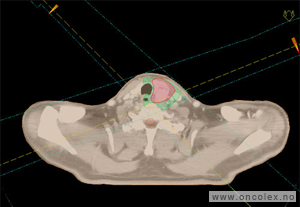

Ved ultralydundersøkelse føres en ultralydprobe inn i skjeden.